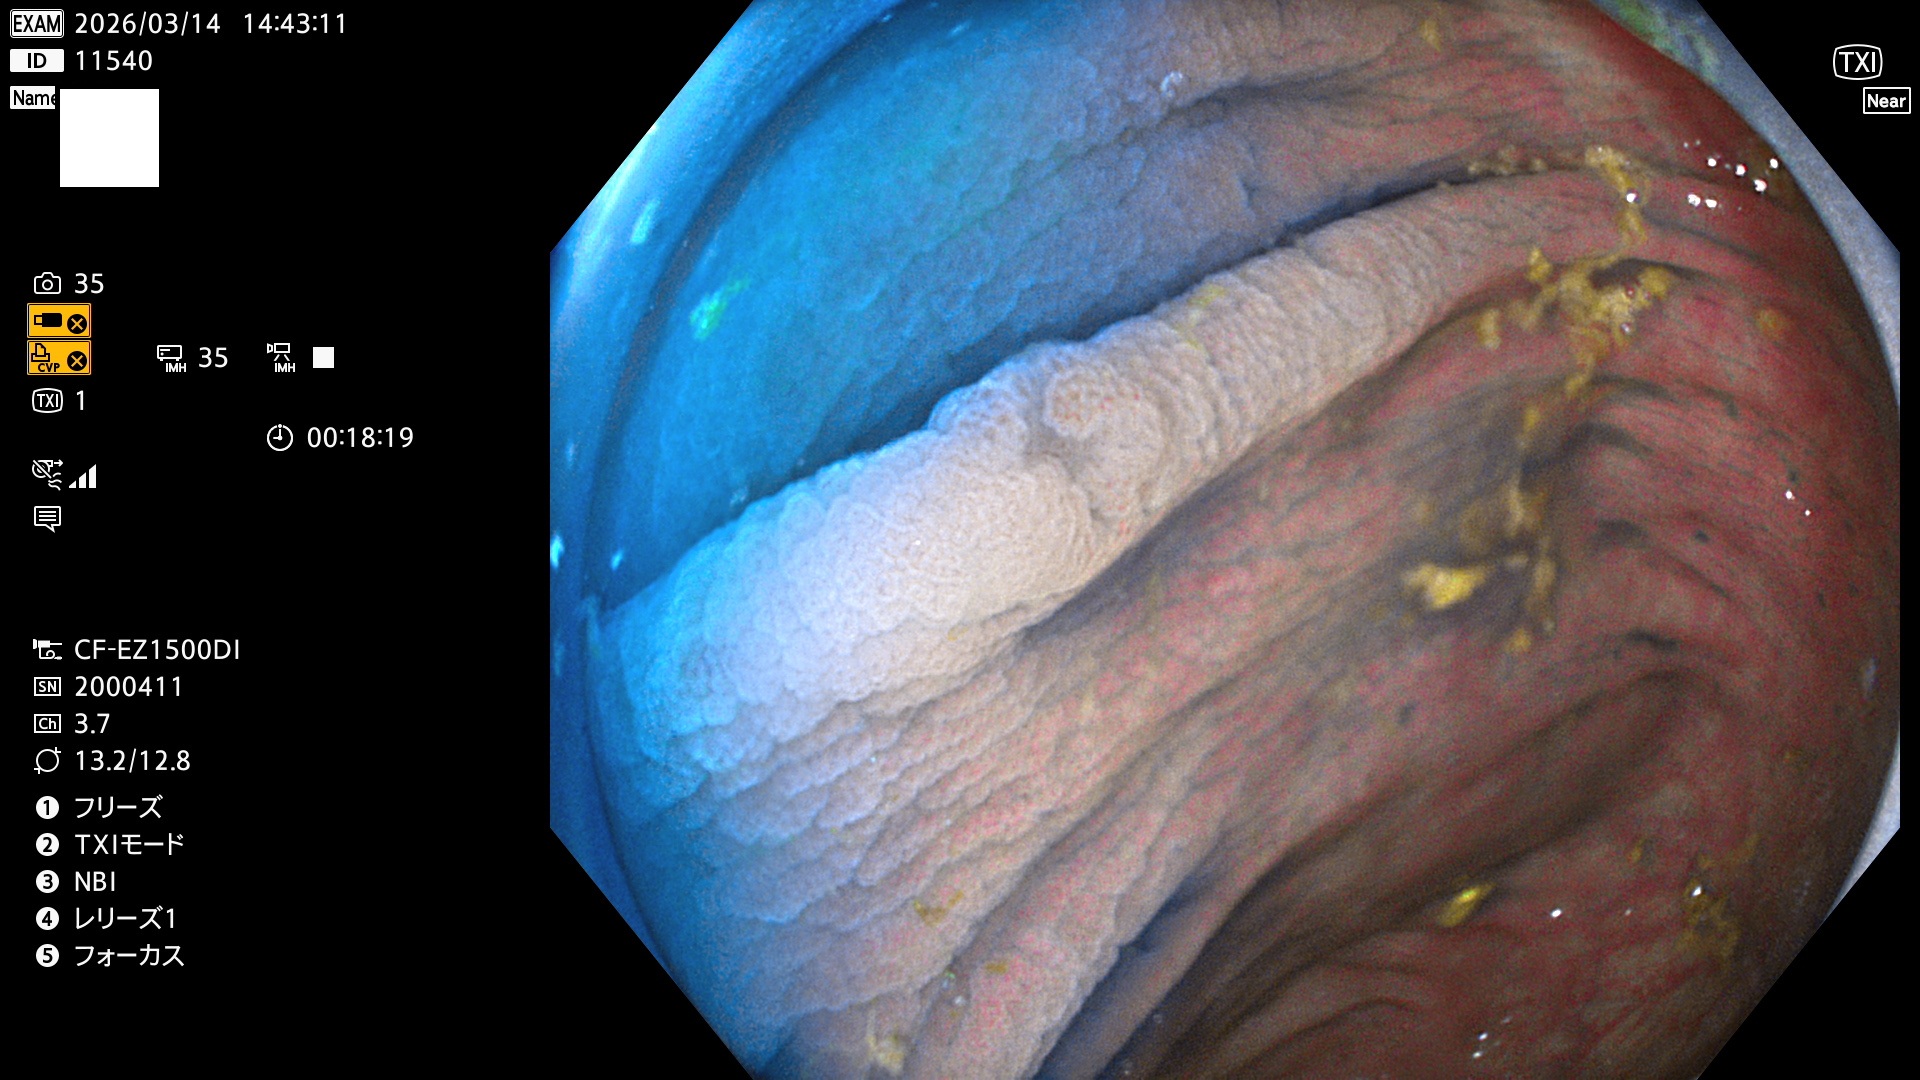

完全に平坦な物をUb、陥凹している物をUcと呼びます。Ubは認識が困難で、Ucはびらん(炎症)と紛らわしいために見落とされやすく、「内視鏡後・大腸癌」の原因になります。

専門的)Uc=De Novo癌? 内視鏡の解像度が低かった時代、このような説もありました。しかし今日の高精度内視鏡では良性の微小なUc型腺腫(APC遺伝子異常の腺腫)が日常的に見つかります。Ucこそが多段階発癌(Adenoma-Carcinoma Sequence)のMain Routeです。

毎週の検査(木・金・土・日)に発見されたUbとUc型・腺腫を、その週の日曜の夜にUPし1週間、提示します。

2026年3月12日〜3月15日の4日間(40件)6個 (Uc_ADR=6個/40人=15%)